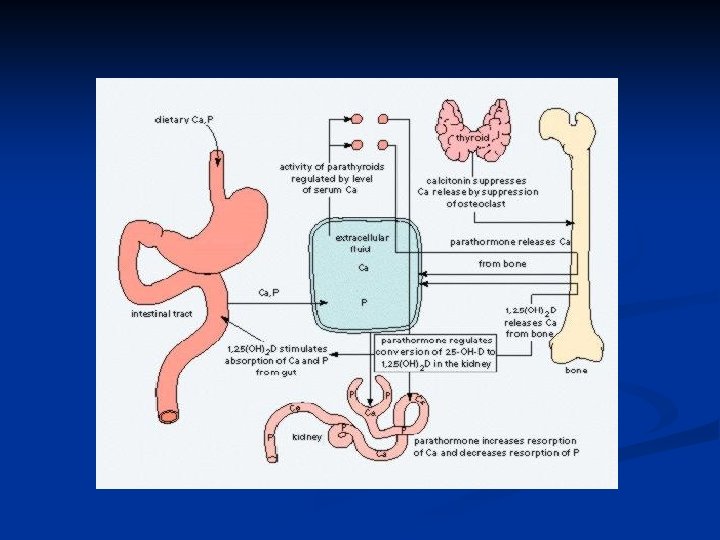

VITAMIN D DEFICIENCY n Vitamin D deficiency leads to decreased absorption of calcium by the GI tract. n As serum calcium starts to fall, secondary hyperparathyroidism occurs.

VITAMIN D DEFICIENCY n Elevated Pth levels may maintain serum calcium in the normal range, but at the cost of phosphaturia, hypophosphatemia and increased bone reabsorption n Low serum phosphate results in inadequate bone mineralization and osteopenia.

VITAMIN D DEFICIENCY n In severe cases, secondary hyperparathyroidism is not adequate to maintain serum calcium levels, and hypocalcemia occurs.

OSTEOMALACIA, RICKETS Normal bone metabolism n CALCIUM 99% in bone. Main functions- muscle /nerve function, clotting. Plasma calcium- 50% free, 50% bound to albumin. n Dietary needs- Kids- 600 mg/day, Adolesc. -1300 mg/day, Adult-750 mg/day, Pregnancy-1500 mg/day, Breastfeeding-2 g/day, Fractures - 1500 mg/day n Absorbed in duodenum (active transport) and jejunum (diffusion), 98% reabsorbed in kidney prox. tubule, may be excreted in stool.

OSTEOMALACIA, RICKETS Normal bone metabolism n n PHOSPHATE 85% in bone. Functions-metabolite and buffer in enzyme systems. Plasma phosphate mainly unbound. Daily requ. 1 -1. 5 g/day

OSTEOMALACIA, RICKETS Regulation of Calcium & Phosphate Metabolism: Peak bone mass at 16 -25 years. Bone loss 0. 3 - 0. 5% per year (2 -3% per year after 6 th decade). 1. Parathyroid Hormone (PTH) 2. Vitamin D 3 3. Calcitonin 4. Other Hormones: Estrogen: Prevents bone loss Corticosteroids: Increases bone loss Thyroid hormones: Leads to osteoporosis Growth hormones: Cause positive calcium balance Growth factors

Biochemistry of Vitamin D 3 – Brief Review Vitamin D 3 (cholecalciferol) is synthesized in the skin, with UV light, from 7 -dehydrocholesterol n Vitamin D 3 is hydroxylated twice – first in the liver, to 25 hydroxycholecalciferol, then in the kidney, to 1, 25 dihydroxycholecalciferol, the most potent form of Vitamin D n

Vitamin D (cont’) n Primary role of Vitamin D n n Increase calcium and phosphate absorption from the intestines Other tissues that Vitamin D acts on Parathyroid glands n Bone, Kidneys n Skin, Brain, Pituitary n Lymphocytes, Tumors n